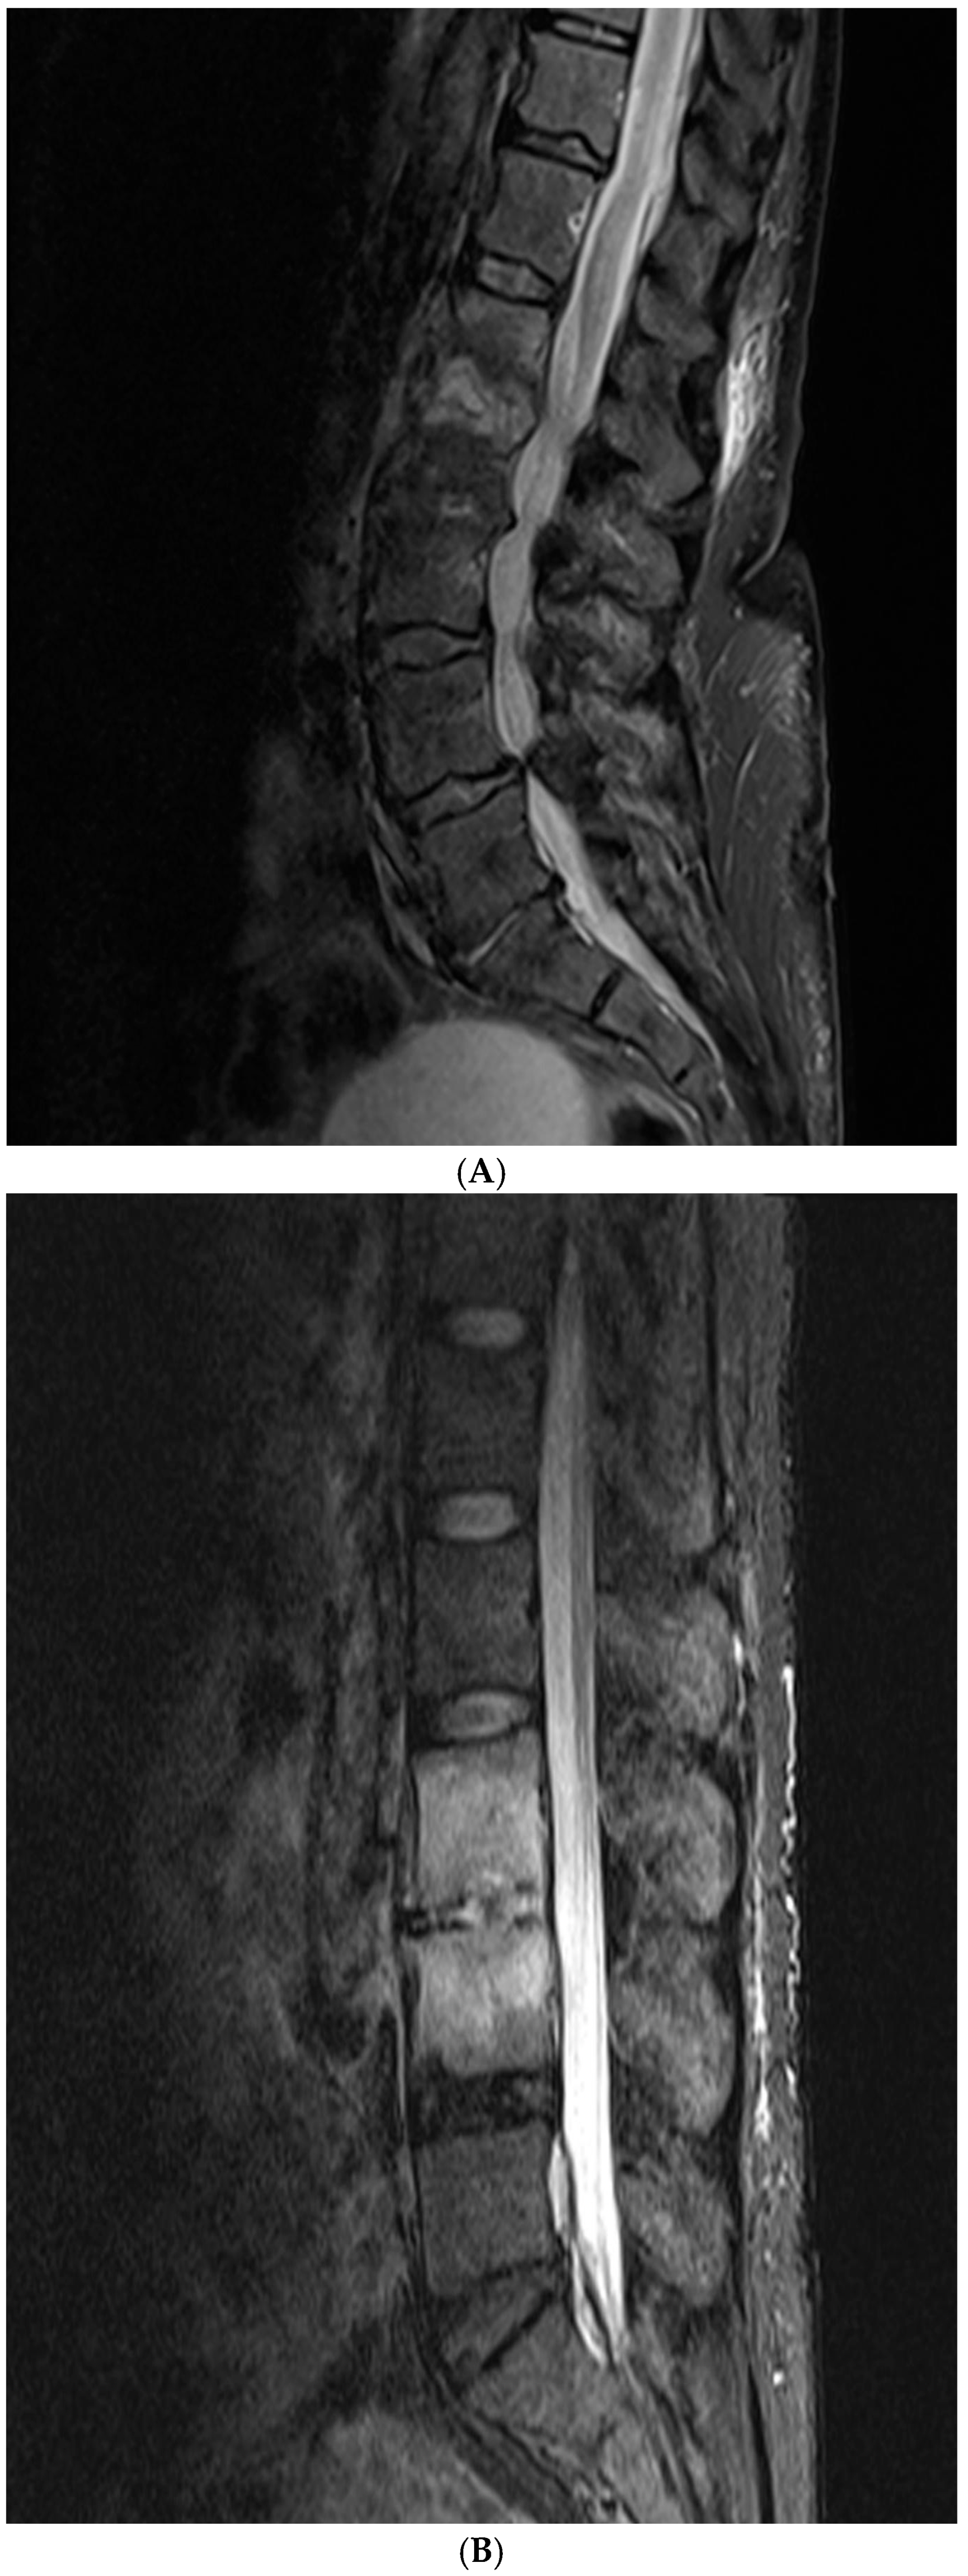

2.2. Imaging Scoring Systems

3.2. Analyses of Imaging Findings

4.2. Imaging Findings